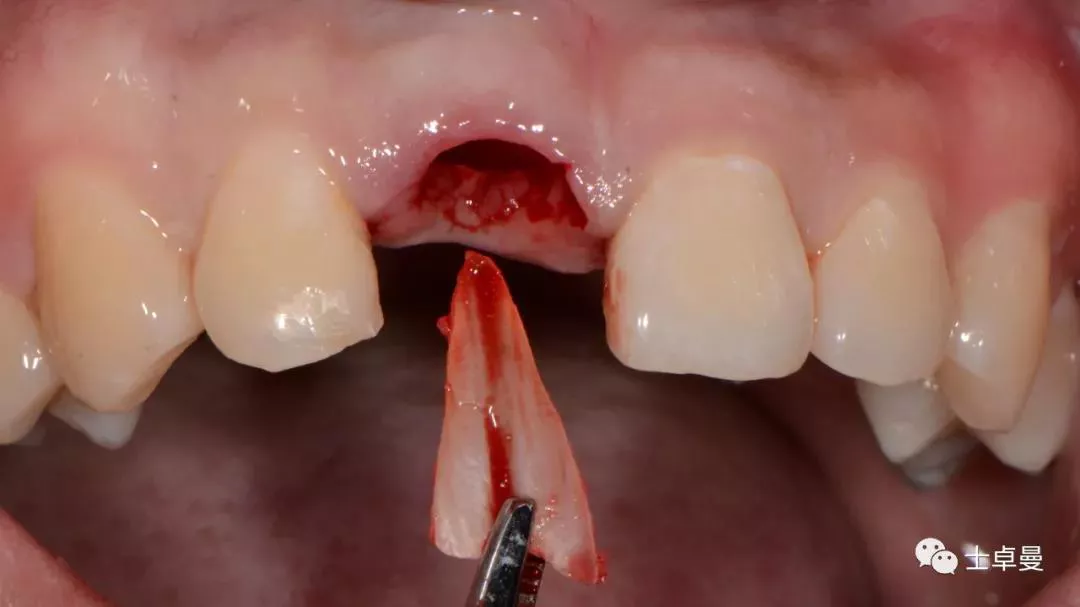

分根

拔出腭侧牙根

保留唇侧牙片

牙周探针探查牙片位置及松动度